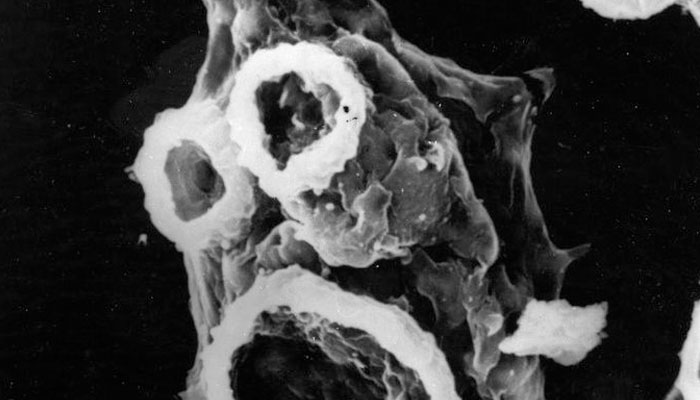

Experts say the disease caused by Naegleria fowleri is a rare and usually fatal brain infection, and exposure to this microorganism occurs during swimming or other water sports, as this protozoan is found in freshwater lakes, rivers and hot springs.

The amoeba travels up the nose to the brain, where it causes severe damage.